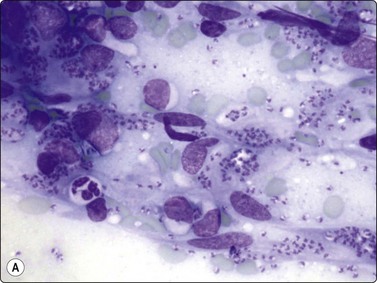

In fungal and cat scratch disease,40 suppurative granulomas with neutrophils interspersed among the epithelioid histiocytes in the granulomas may be present (Fig. 18.2).

image

Fig. 18.2 Suppurative granuloma

Neutrophils infiltrate epithelioid granuloma consisting of epithelioid histiocytes in background of neutrophils (Giemsa, ×600).